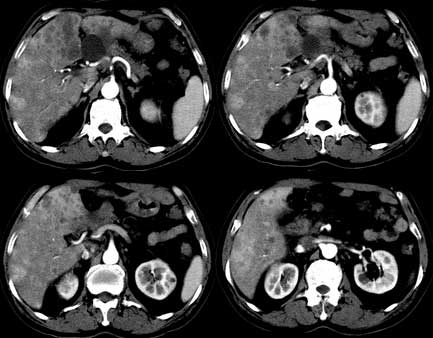

患者 男性 65岁,2005年8月行胆管癌切除术(切除胰头 胆囊及十二指肠),今行ct复查,请会诊,有没有复发?(近期患者发烧,重度黄疸)

考虑胆囊癌术后复发及肝转移,肝门区胆管扩张明显,左肾囊肿。

是单纯复发还是复发伴肝内转移?我个人认为应当再考虑一下,并倾向于后者。肝总管下端内、后侧见不规则软组织块影,部分侵入肝总管内。其边缘凸凹不平且模糊不清,渐进性不均匀强化。肝总管于此处管径突然变小,其上肝总管显著扩张,内见较均匀液性密度,管壁也很光整。肝内多发低密度病灶用复发引起的肝内胆管扩张显然不能解释的通,病灶分布与胆内胆管的走行不一致。而且随着时间的延续病变更加清晰,没有强化,部分还可见牛眼征。

肯定是:胆管复发并肝内广泛转移,还有肝及胆总管周围网膜炎性改变。腹腔干后第三层面腹膜后血管间结节状影,淋巴结肿大可能,这上面没法看清!

考虑复发并转移,肝门区胆管扩张,左肾多发囊肿可能.腹腔淋巴结转移.